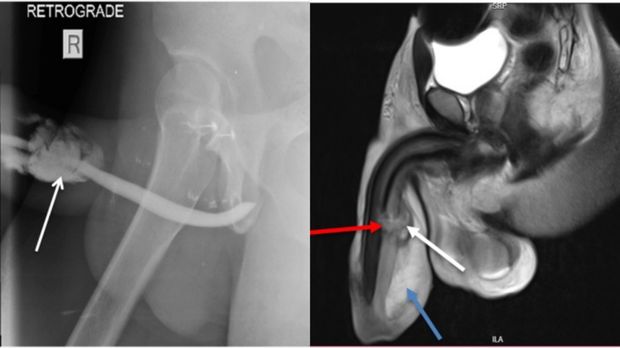

Hasil MRI fraktur penis atau patah penis pria di Tanzania Foto: Science Direct |

Dari hasil MRI, penis pria berusia 36 tahun itu 'patah' di tiga bagian yaitu sepanjang tunica albuginea, corpora cavernosa dan corpus spongiosum, yang merupakan jaringan ereksi.

Selain itu, pria tersebut juga mengalami robekan pada sebagian uretra, saluran yang membawa air mani dan urine keluar dari penis.